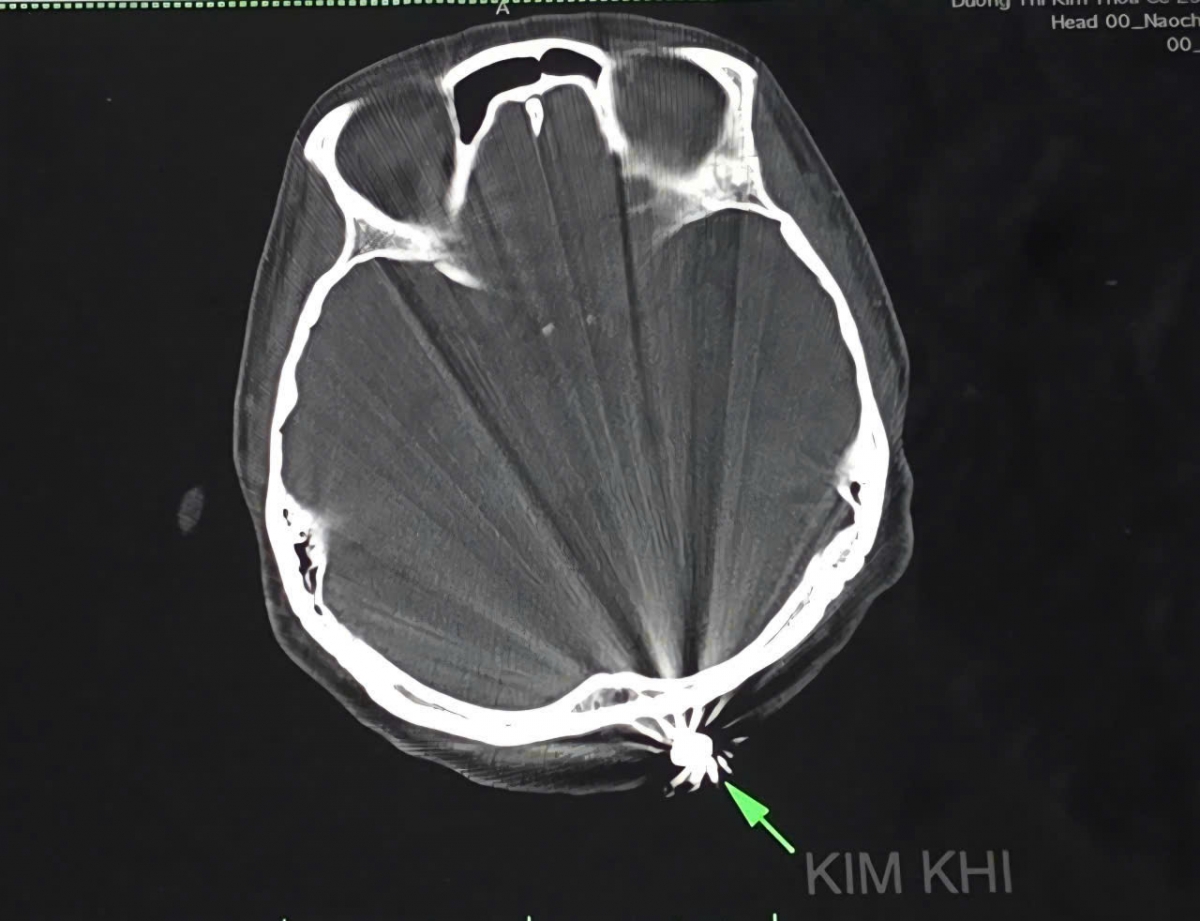

Sau khi hội chẩn, các bác sĩ khoa ngoại Thần kinh quyết định tiến hành phẫu thuật lấy dị vật và xử trí tổn thương. Mở rộng vết mổ khoảng 3cm lấy ra dị vật kim khí hình đầu đạn 0,5x 0,3cm.

Hình ảnh dị vật chụp phim CTScan